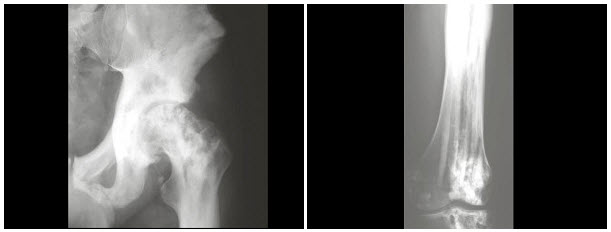

女,18岁,左下肢肿痛,活动后加重,关节僵硬,结合图像,最可能的诊断是()

A.蜡油骨病

B.骨斑点症

C.条纹状骨病

D.石骨病

E.肥大性骨关节病